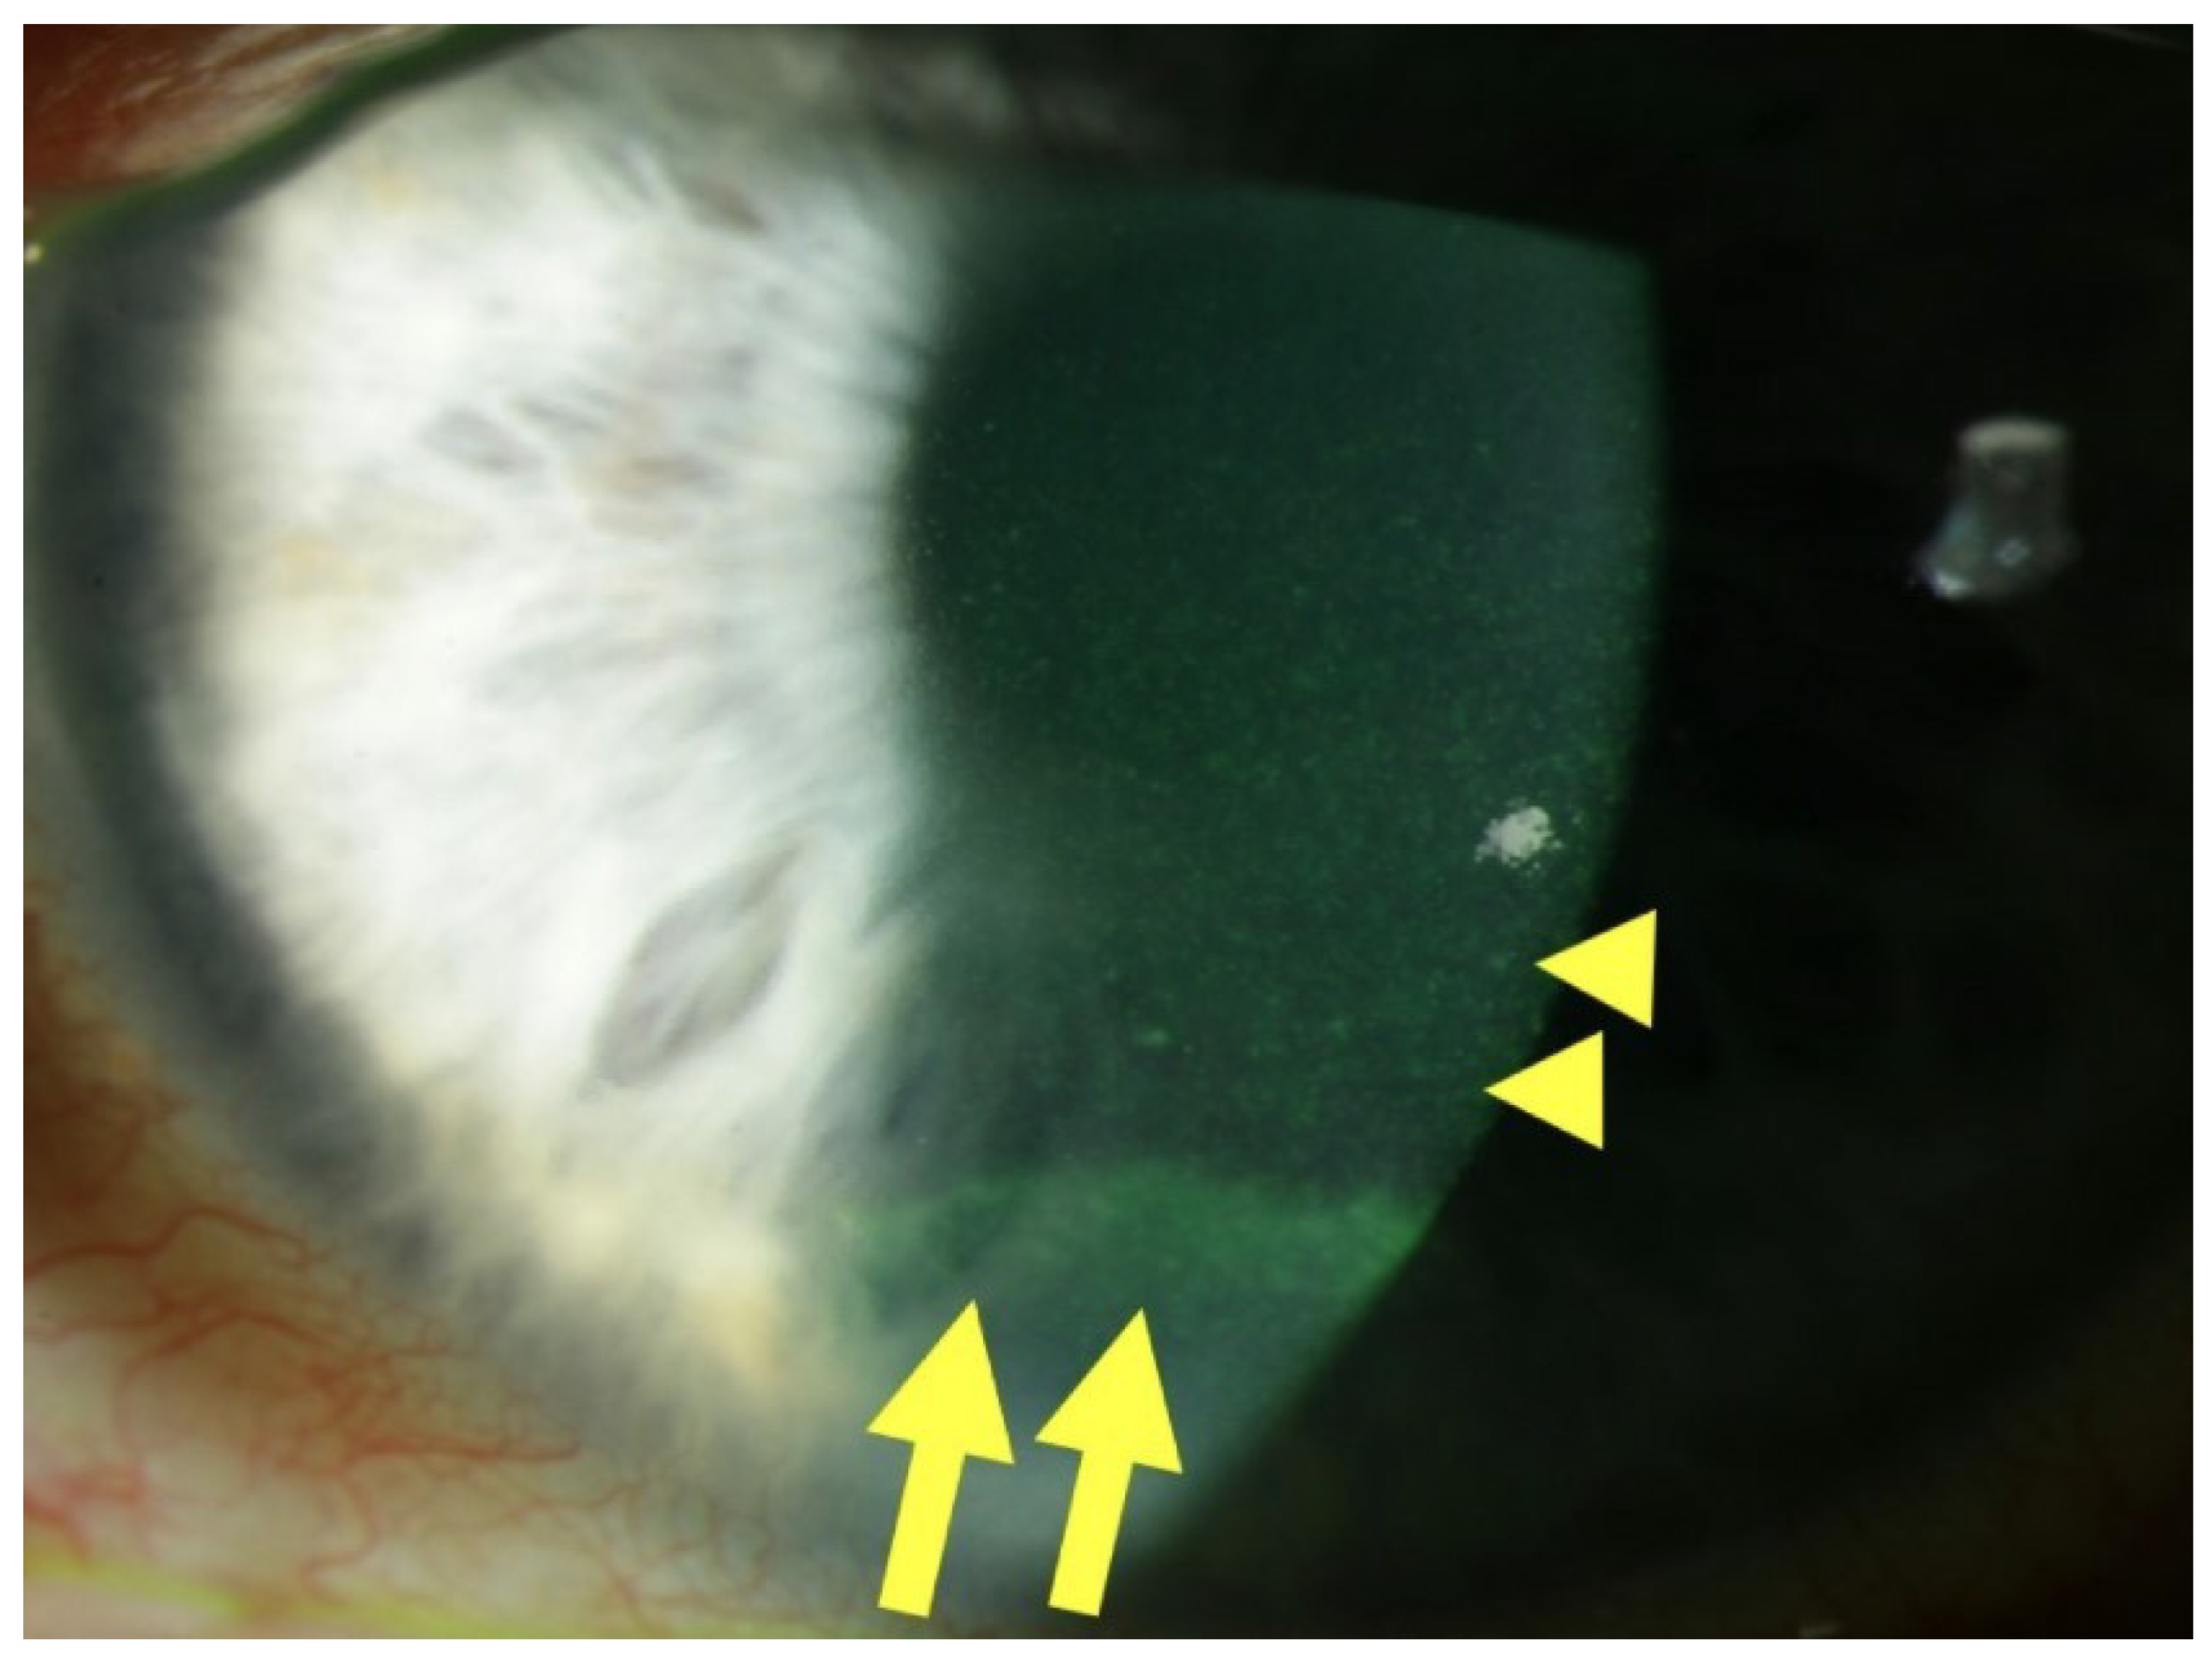

DEK manifests through a spectrum of clinical signs arising from epithelial dysfunction. A hallmark finding is superficial punctate keratitis (SPK), characterized by fluorescein-positive punctate epithelial erosions. A slit-lamp photograph suggestive of surface changes associated with DEK is shown in Figure 1.

Figure 1.

Slit lamp photograph of a patient with diabetic keratopathy. Centrally, fluorescein staining reveals SPKs (yellow arrowheads), as well as an epithelial ridge or pseudo-dendrite, indicative of a recently closed erosion (yellow arrows), in the inferior third of the cornea. From “Diabetic Keratopathy: Redox Signaling Pathways and Therapeutic Prospects” by Buonfiglio, F.; Wasielica-Poslednik, J.; Pfeiffer, N.; Gericke, A. Antioxidants 2024, 13, 120, Introduction, Figure 1, (https://doi.org/10.3390/antiox13010120 (accessed on the 11 March 2024)). CC BY. [4].